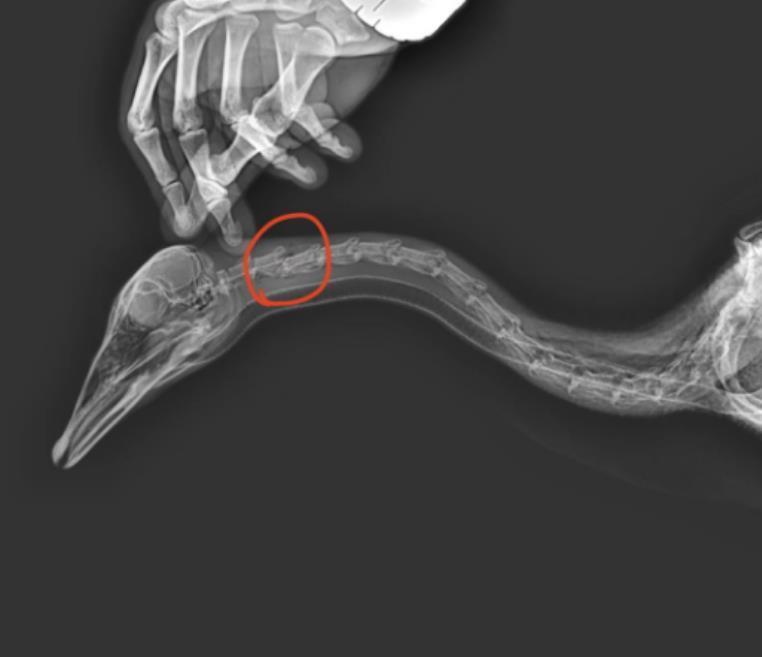

随后,北青报记者致电河北省园博园园区,工作人员表示,该斑头雁是园区人工饲养,被游客踢中后倒地不起,虽然园区工作人员第一时间赶到现场,拨打了报警电话,并将大雁送医,可惜中途大雁死亡。根据拍摄CT显示,大宝颈部骨头断裂,胸腔肺部有凹陷。